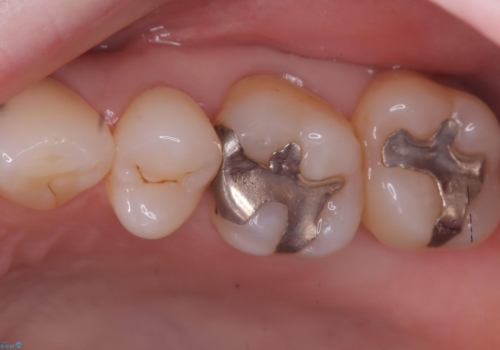

- 主訴:詰め物と歯の境目によごれがいつも溜まっている。フロスを通すと引っかかる。

保険適用のメタルインレーと歯質の境目が、歯質が欠けてしまったのか大きなくぼみ汚れが停滞しやすい状態になっていました。歯冠色材料でのやり替えを希望されたため、セラミックインレーでのやり替えとなりました。

左上6番に入っている保険適応のメタルインレーと歯質との境目(近心側室エリア)に不適部位を認め、そのくぼみに汚れが停滞しやすい状態となっていました。